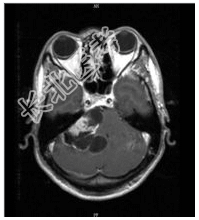

- [材料题] 患者男,37岁,右耳听力丧失数月。查体:右耳听力丧失,视力正常,余神经体征阴性。行头颅MR平扫及增强检查。